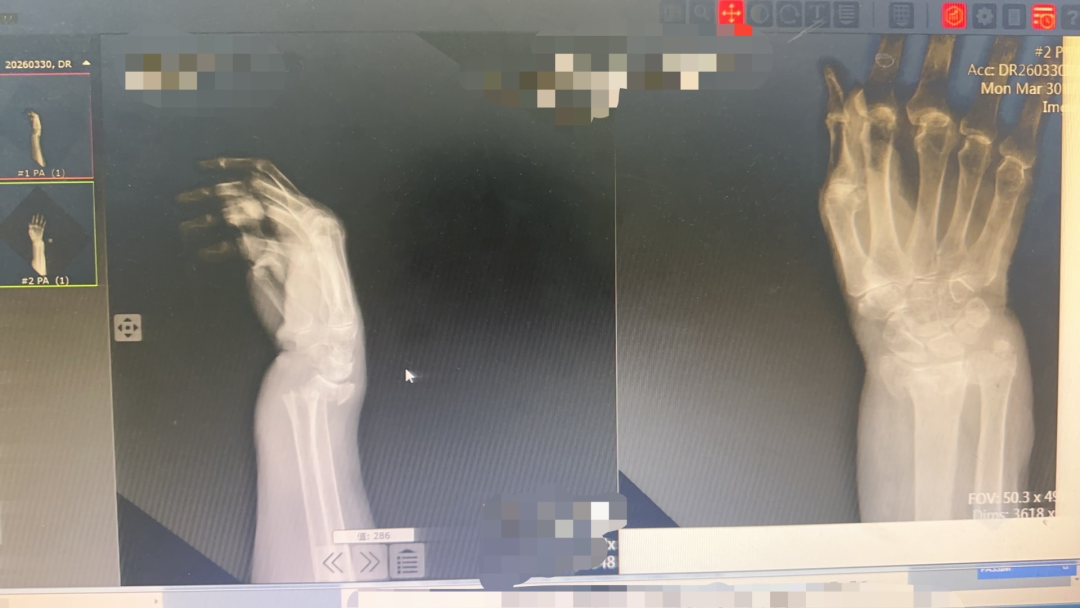

接诊的薛安邦主治医师第一时间为田奶奶仔细检查。老人的右腕部肿胀明显,呈现出典型的“餐叉样”畸形,一按就疼,腕关节活动完全受限。随后的X线片证实了诊断:右尺骨远端骨折伴桡骨远端骨折,骨折端移位明显。如果不及时处理,不仅会影响手腕功能,长期制动还可能引发压疮等一系列并发症,对90岁高龄的老人来说,风险极大。

复位后,团队立即为老人进行石膏外固定。复查X线片显示:骨折端对位对线良好,达到了解剖复位标准。田奶奶腕部畸形完全消失,疼痛明显缓解。